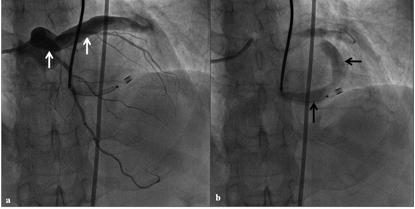

Figure 2. Selective left coronary angiogram in right anterior oblique cranial projection revealed aneurysmally dilated left main and circumflex coronary artery (white arrows) in the early phase (A) and fistulous tract draining into coronary sinus (black arrows) in the late phase (B) (click thumbnail to view larger image).

The selective left coronary angiogram revealed a large coronary artery fistula originating from the left circumflex coronary artery and draining into the coronary sinus (Figures 2A and 2B; Video 1). Both left main and circumflex coronary arteries were aneurysmal with tortuous fistulous tract. There was no evidence of significant atherosclerotic coronary artery disease.